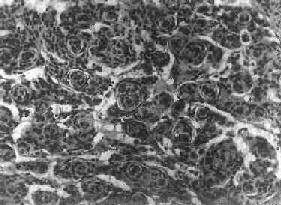

肉眼观,组织呈鱼肉状,色灰红。镜下,肿由圆形、椭圆形或胡萝卜形细胞构成,胞核着色深,胞浆少而边界不清楚,有多少不等的核分裂像。细胞密集,间质中有纤细的纤维,血管不多。细胞环绕一个嗜银性纤细的神经纤维中心作放射状排列形成典型的菊形团(图16-26),这对髓母细胞的病理诊断有一定的意义。细胞具有向神经元及神经胶质双向分化的潜能,既能向神经母细胞、节神经细胞分化,也能向胶质母细胞、星形胶质细胞分化。如细胞侵入软脑膜,可在蛛网膜下腔脑脊液中广泛播散转移。

图16-26 髓母细胞

细胞较小,着色深,密集排列,有菊形团形成